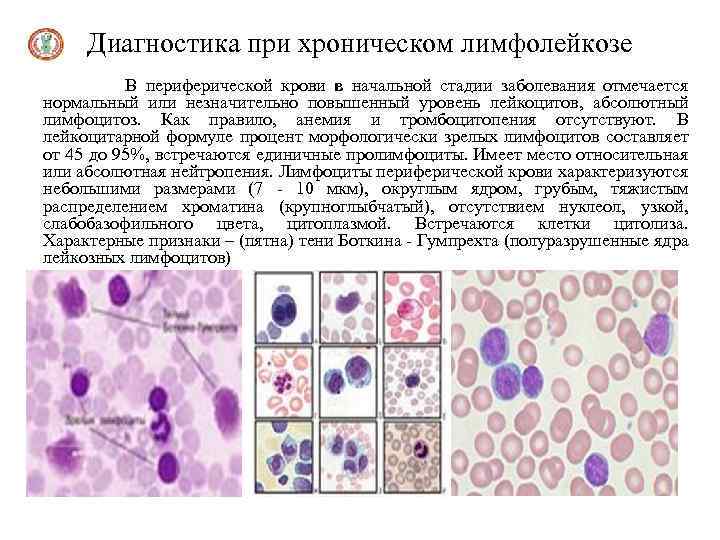

Диагностика при хроническом лимфолейкозе В периферической крови в начальной стадии заболевания отмечается нормальный или незначительно повышенный уровень лейкоцитов, абсолютный лимфоцитоз. Как правило, анемия и тромбоцитопения отсутствуют. В лейкоцитарной формуле процент морфологически зрелых лимфоцитов составляет от 45 до 95%, встречаются единичные пролимфоциты. Имеет место относительная или абсолютная нейтропения. Лимфоциты периферической крови характеризуются небольшими размерами (7 - 10 мкм), округлым ядром, грубым, тяжистым распределением хроматина (крупноглыбчатый), отсутствием нуклеол, узкой, слабобазофильного цвета, цитоплазмой. Встречаются клетки цитолиза. Характерные признаки – (пятна) тени Боткина - Гумпрехта (полуразрушенные ядра лейкозных лимфоцитов)